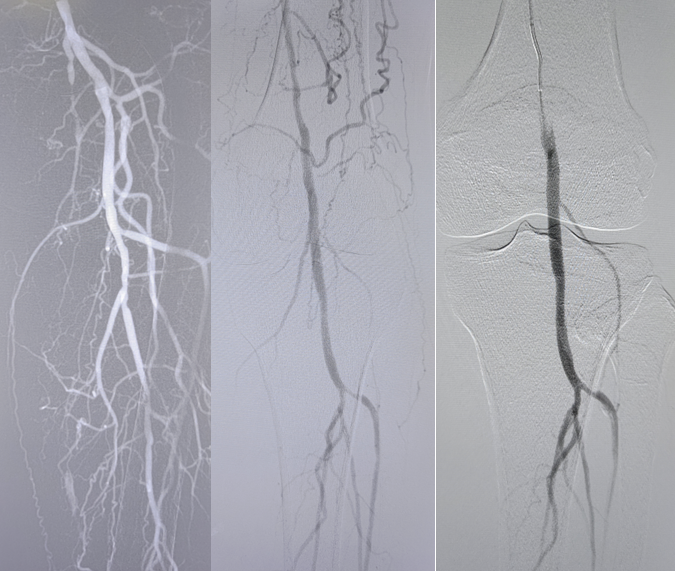

病例2(股腘动脉长段闭塞):

另一例长段闭塞病变,IVUS证实导丝真腔通过后,指导术者选择了合适尺寸的Rotarex导管进行减容,联合普通球囊(POBA)预扩及DCB治疗,获得了满意的管腔,避免了支架植入。

图:导丝通过后3mm球囊预扩

图:多处假腔通过,遂5mm球囊预扩

图:一期支架植入